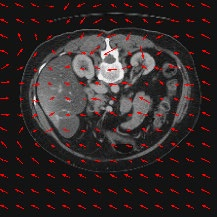

Transformers have made remarkable progress towards modeling long-range dependencies within the medical image analysis domain. However, current transformer-based models suffer from several disadvantages: (1) existing methods fail to capture the important features of the images due to the naive tokenization scheme; (2) the models suffer from information loss because they only consider single-scale feature representations; and (3) the segmentation label maps generated by the models are not accurate enough without considering rich semantic contexts and anatomical textures. In this work, we present CASTformer, a novel type of generative adversarial transformers, for 2D medical image segmentation. First, we take advantage of the pyramid structure to construct multi-scale representations and handle multi-scale variations. We then design a novel class-aware transformer module to better learn the discriminative regions of objects with semantic structures. Lastly, we utilize an adversarial training strategy that boosts segmentation accuracy and correspondingly allows a transformer-based discriminator to capture high-level semantically correlated contents and low-level anatomical features. Our experiments demonstrate that CASTformer dramatically outperforms previous state-of-the-art transformer-based approaches on three benchmarks, obtaining 2.54%-5.88% absolute improvements in Dice over previous models. Further qualitative experiments provide a more detailed picture of the model's inner workings, shed light on the challenges in improved transparency, and demonstrate that transfer learning can greatly improve performance and reduce the size of medical image datasets in training, making CASTformer a strong starting point for downstream medical image analysis tasks.